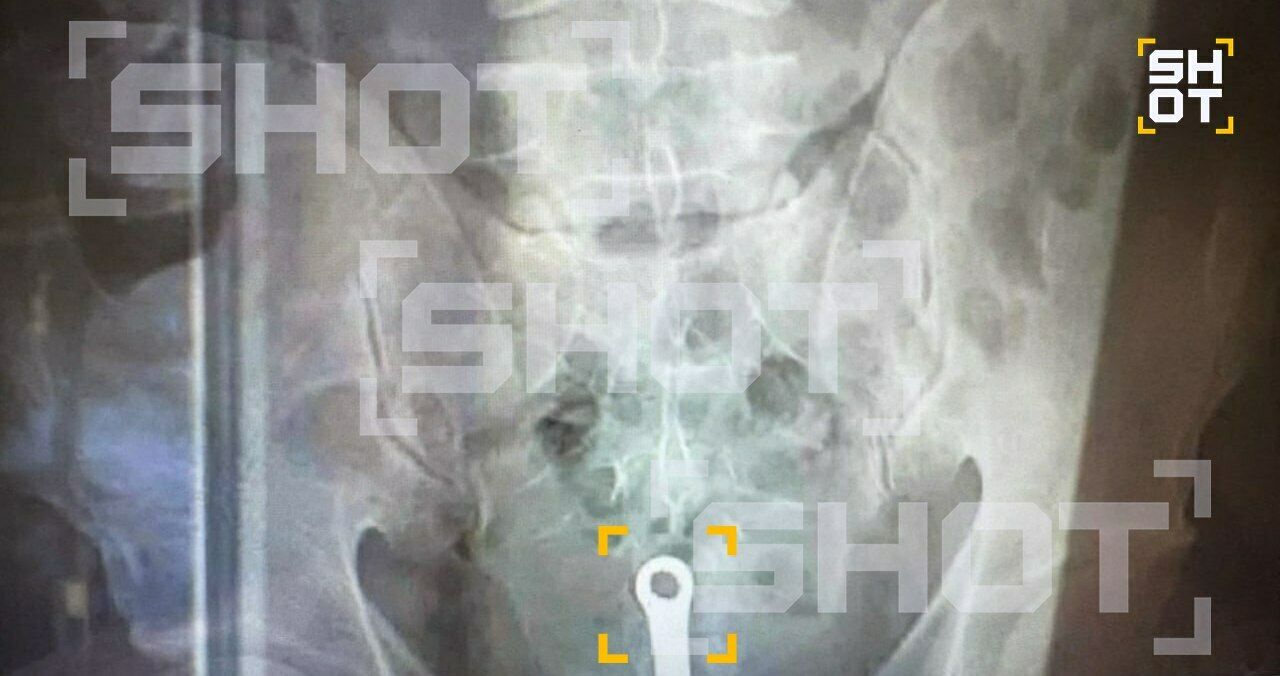

В Уфе врачи спасли пациента, у которого в заднем проходе застрял ершик для унитаза.

Некоторое время к врачам обратился 32-летний житель Уфы. Мужчина рассказал, что в его прямой кишке застрял ершик для чистки унитаза.

В итоге уфимец оказался на операционном столе. Хирурги извлекли посторонний предмет из организма пациента и вскоре отпустили его домой. Информацией делится Telegram-канал SHOT.

Фото: Telegram / SHOT